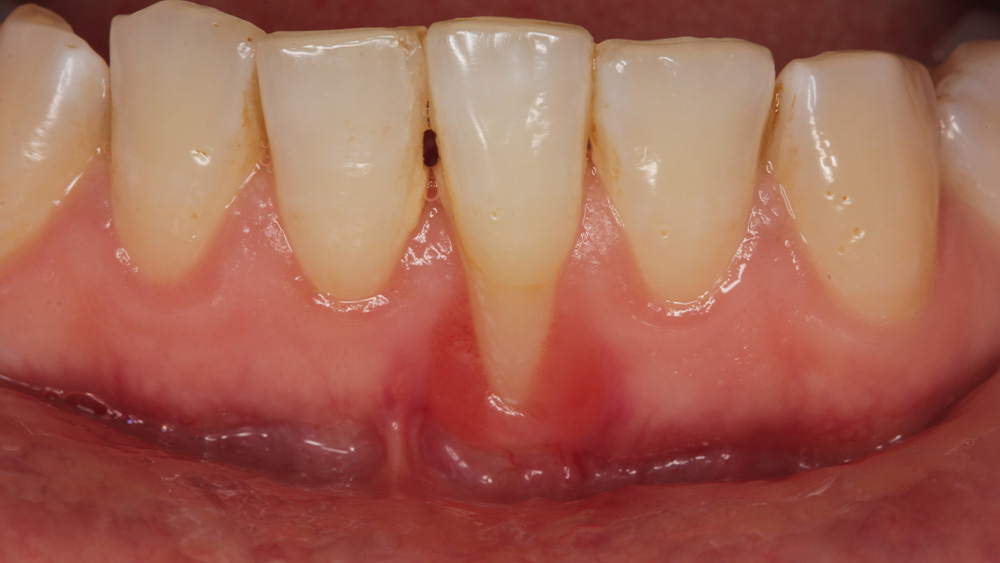

当院では、口腔内カメラでお口の中を撮影し、その画像を大きなモニターに映しながらご説明いたします。

歯石の付着状況や歯ぐきの炎症具合などを視覚的に確認いただくことで、「なぜこの治療が必要なのか」「これからどうなっていくのか」をより深くご理解いただけると考えております。

歯周病の初期段階では、歯と歯ぐきの境目や、歯周ポケットと呼ばれる隙間に溜まった歯垢や歯石を取り除くことが中心となります。

超音波スケーラーなどの機器を用いて歯石を除去し、SRP(スケーリングルートプレーニング)という方法で歯の根の表面を滑らかに清掃することで、細菌が再付着しにくい環境を整えます。